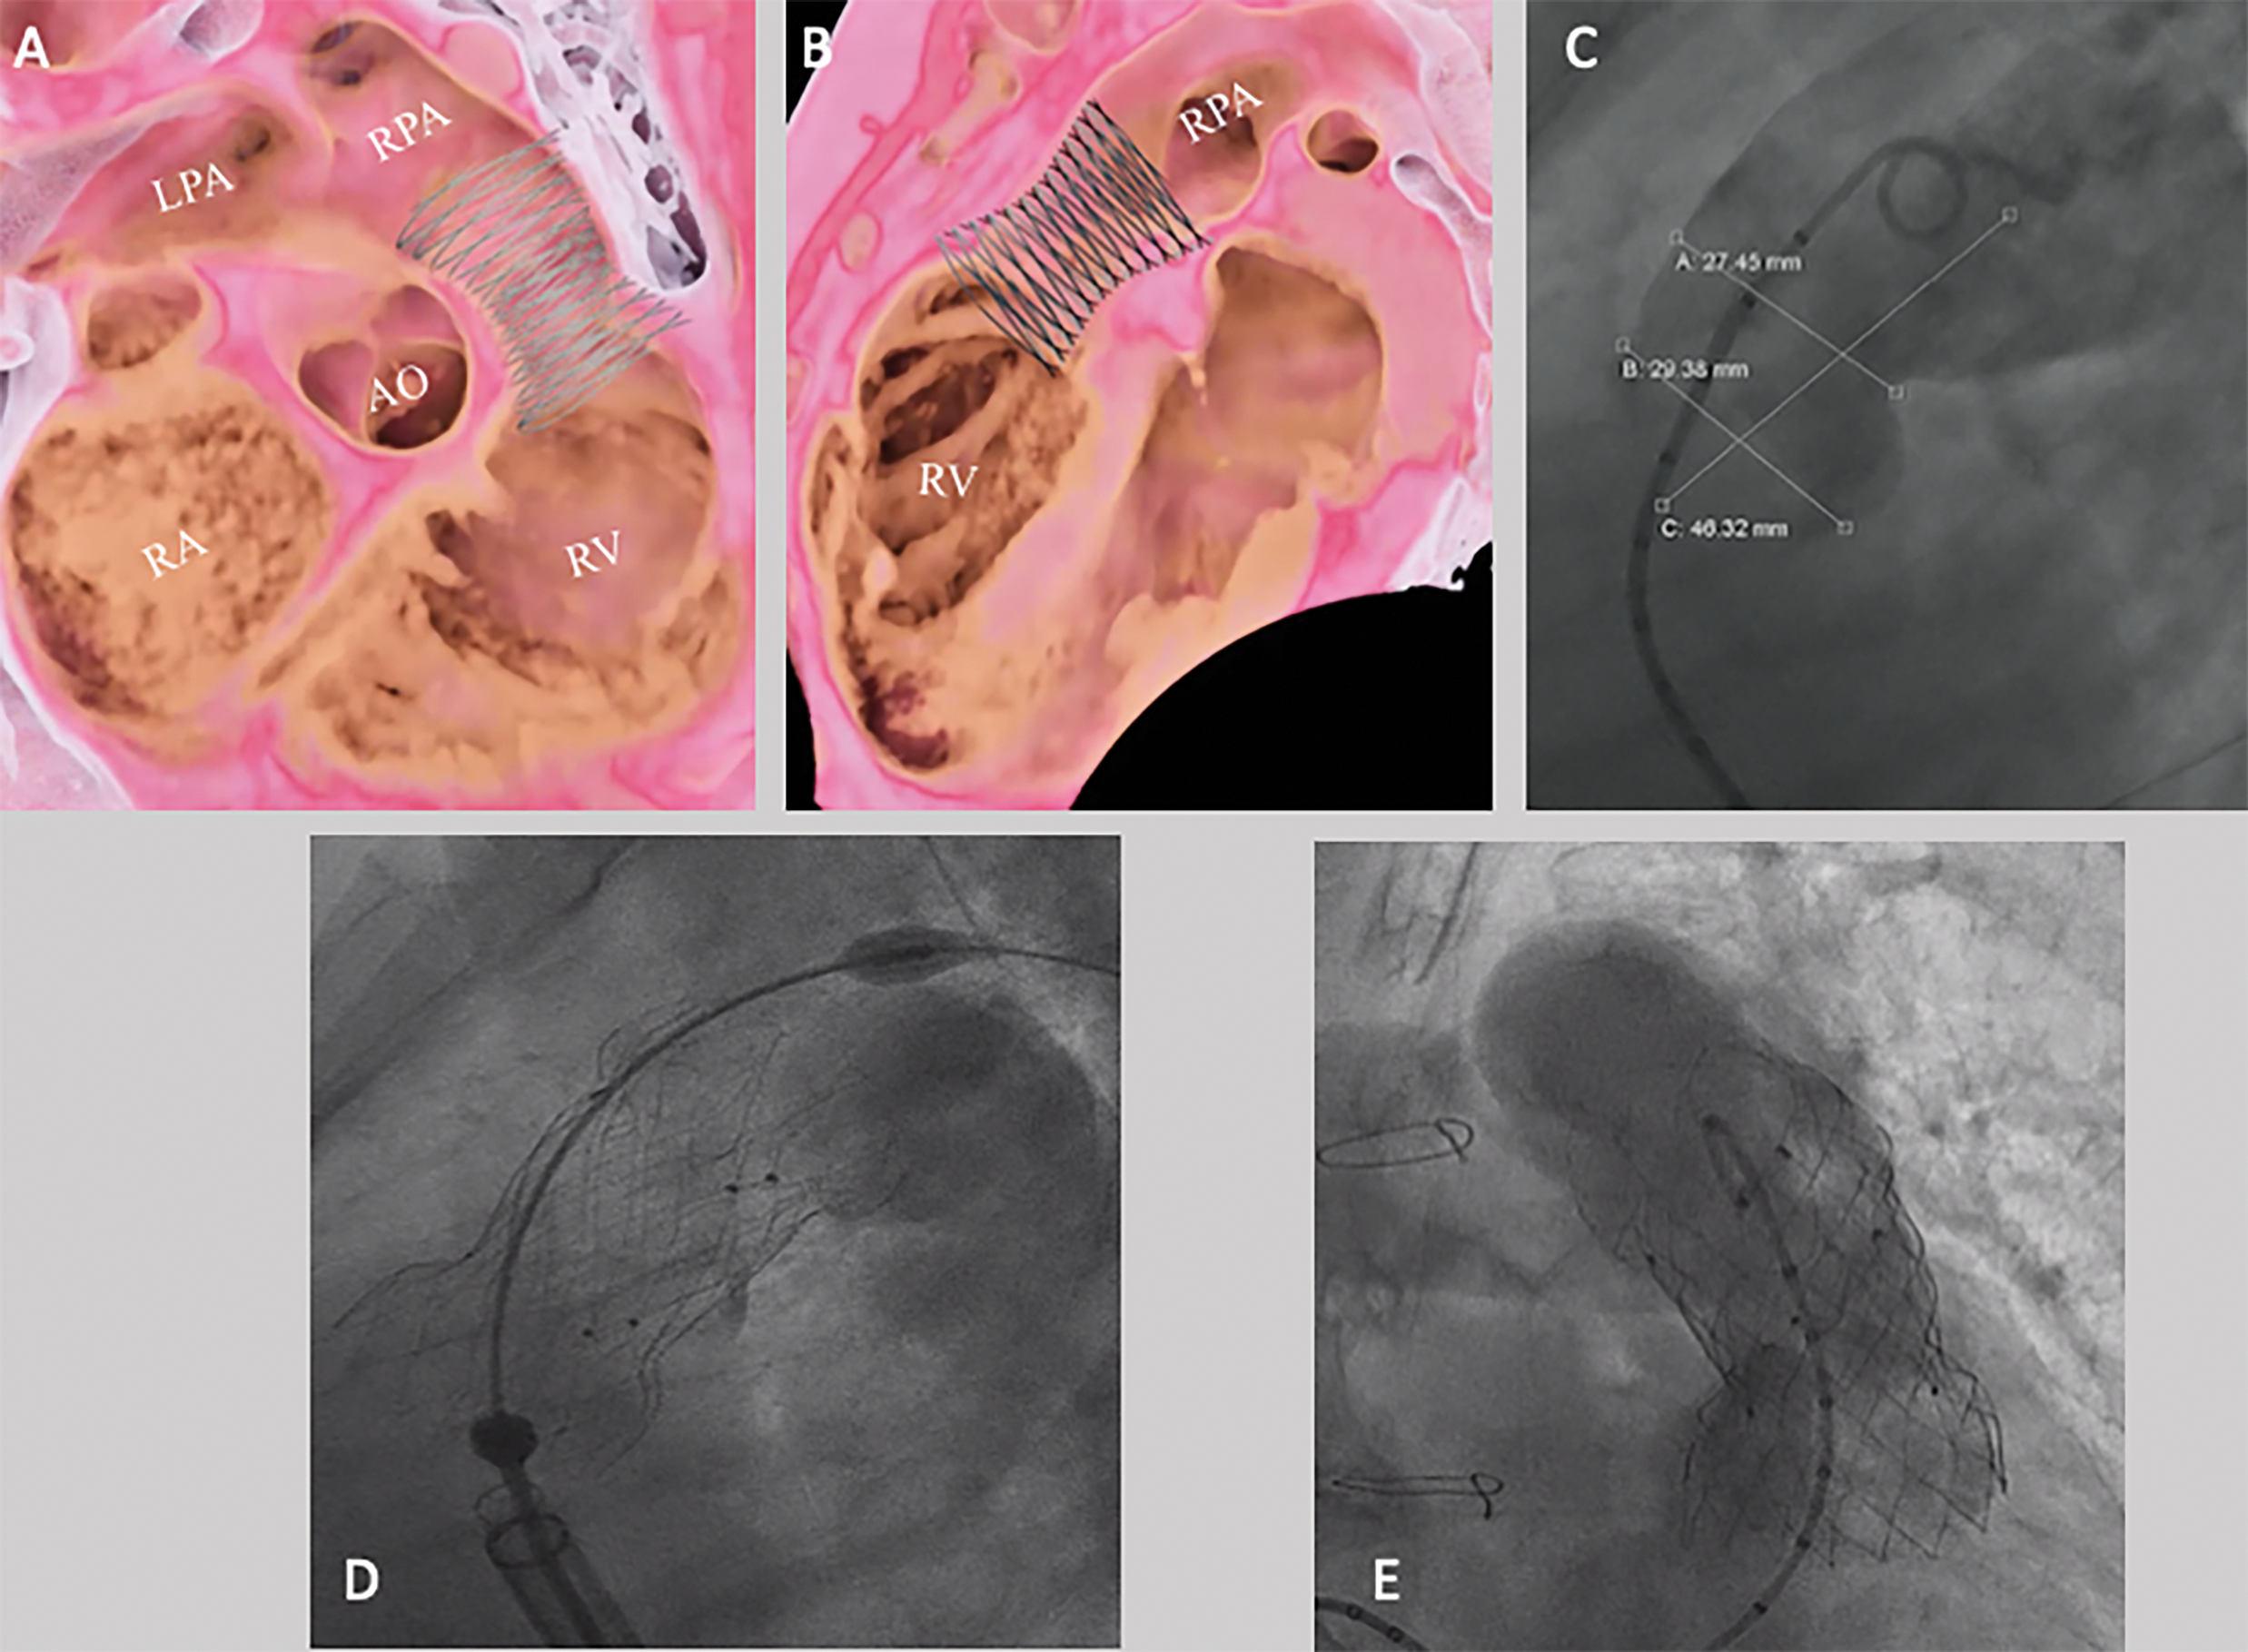

Anchorage is achieved through a flared, uncovered distal end, which ensures adequate perfusion of pulmonary artery branches in the event of jailing. The valve is typically deployed in or just below pulmonary artery bifurcation, with the symmetric proximal end, covered to close possible paravalvular leaks. The proximal landing zone should ideally be positioned near (or better above) the native (or former) pulmonary valve annulus. The valve is available in five sizes, corresponding to the smallest (valved) stent diameter, ranging from 28 to 36 mm in 2 mm increments. The edges of the device are about 10 mm larger than the valve diameter. In addition, there are two lengths available for any diameter, 25, and 30 mm, indicating the length of the central (cylindrical) segment of the device. The cylindrical segment of the valve is marked with six radiopaque markers, to facilitate the deployment maneuvers [25]. The funnel-shaped edges are both 15 mm in height. The valve must be loaded into the delivery system using a dedicated crimping system. To improve the ductility of the device, it should be manipulated in an iced sterile saline solution, to facilitate crimping maneuvers. The valve is secured to three hooks located on the proximal edge of the stent similar to the S3 Sapien valve, this valve is advanced in a 26 Fr Gore®® DrySeal long-sheath (Fig. 3). Once deployment is started, the valve can be retrieved when up to 75% of the device is deployed.

Figure 3: Venus P valve implantation. Virtual reality simulation of device implantation based on CT, in right anterior oblique (A) and lateral (B) views. (C) RVOT angiography demonstrating a narrowest diameter of 27.5 mm. (D) A 34 mm × 25 mm Venus P valve was implanted. (E) Final RVOT angiography demonstrated an effective device function. AO: Aorta, LPA: Left pulmonary artery, RPA: Right pulmonary artery, RV: Right ventricle, RA: Right atrium

In challenging anatomies, hybrid procedures have emerged as a less invasive option, offering the potential to reduce surgical risks, enhance procedural feasibility, and improve overall outcomes [63]. Percutaneous implantation of the pulmonary valve through peripheral vascular access may be limited by factors such as poor venous access, low patient weight hemodynamic or rhythmic instability, and huge RVOT sizes [64]. In such cases, a hybrid approach might be considered to mitigate procedural risk, when re-do surgery might result in challenging or contraindicated (Fig. 4).

Figure 4: Hybrid procedure to implant a 25 Harmony TPV. (A) RVOT size by CT data. (B) Virtual renderings, CT based, of Harmony deployment. (C) Device deployment. The valve was secured through a suture on the distal part of the stent by a left anterior thoracotomy, while the proximal edge of the device was still anchored to the suture loops. (D) Final fluoroscopy after complete device deployment